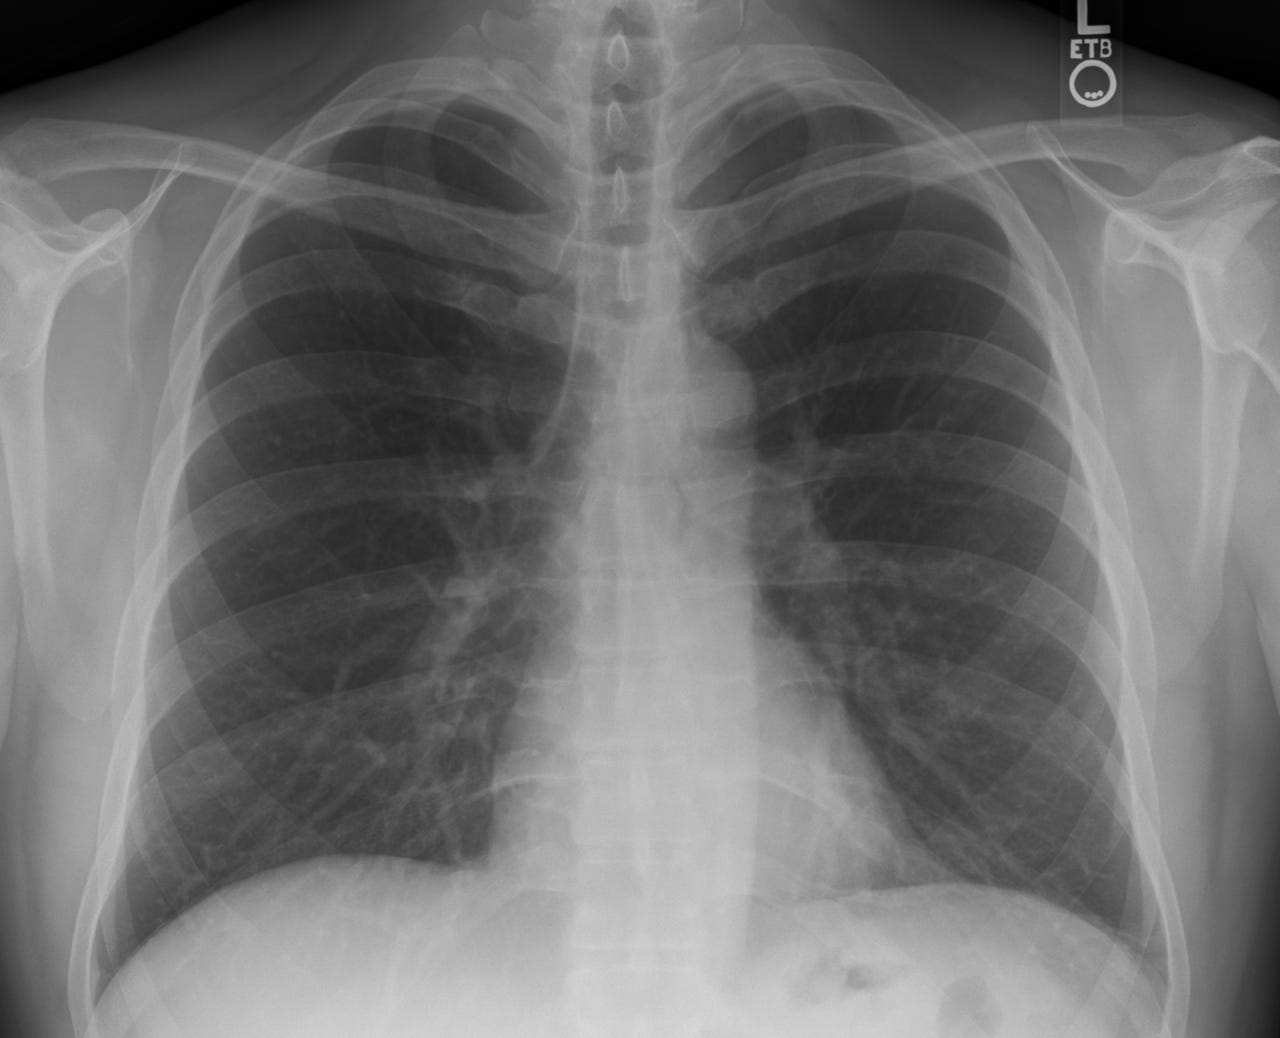

The above image isn’t too hard to decipher. Most people would recognise it as an X-ray of someone’s chest, showing ribs, some vertebrae and what look like shoulders. With a bit more knowledge, you might also spot the clavicle, sternum and outline of the heart, as well as notice that nothing looks broken or fractured. A professional radiologist would, of course, see far more: they might be able to comment on the person’s age, size, or signs of infection or cancer. They would see things that a layperson would not.

If we ever need an X-ray or a CT scan, we’d only want a true radiologist to be interpreting it. If a colleague is going to observe us teaching and give us feedback, we should be able to expect the same level of expertise.